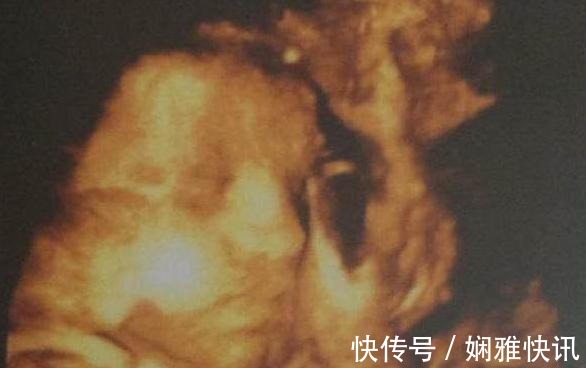

一位怀孕7个月的孕妈去产检,在前6个月的时候,一切正常,胎儿发育的很健康,但是到了第7个月的时候,就发现胎儿在孕妈肚子里“捂着鼻子”,并且表情也有些痛苦。医生非常惊讶,从事医生这个行业这么多年,但是却没有见过这样的胎像,由于胎儿异常,医生断定肯定是出现了问题,所以便开始查找原因,询问孕妈这段时间都做了什么。